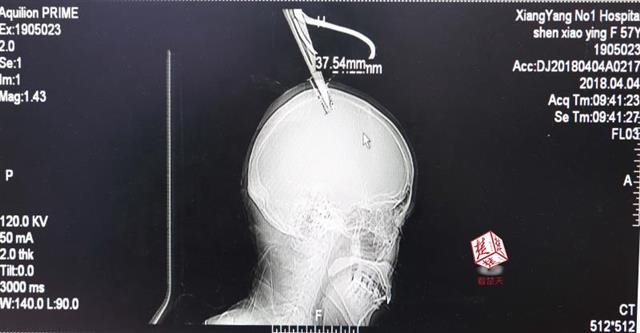

醫(yī)生檢查發(fā)現(xiàn),剪刀刀尖斜嵌在沈某顱骨里,離腦髓只有兩三毫米。所幸是斜著插進(jìn)去,如果是垂直刺入,很有可能造成癱瘓。

4月4日清晨,襄陽(yáng)市樊城區(qū)太平店鎮(zhèn)57歲的農(nóng)村婦女沈某,在采摘香椿嫩芽時(shí),綁在竹桿上的剪刀因竹子腐朽不慎折斷,剪刀斜插入頭顱。經(jīng)過(guò)及時(shí)搶救,目前脫離生命危險(xiǎn)。

醫(yī)生檢查發(fā)現(xiàn),剪刀刀尖斜嵌在沈某顱骨里,離腦髓只有兩三毫米。所幸是斜著插進(jìn)去,如果是垂直刺入,很有可能造成癱瘓。最終經(jīng)過(guò)手術(shù),剪刀被取出,沈某目前仍在ICU進(jìn)一步觀(guān)察。